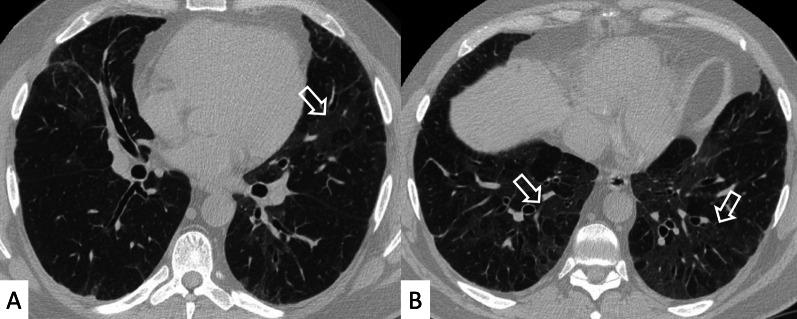

Connective tissue diseases (CTDs) include a spectrum of disorders that affect the connective tissue of the human body; they include autoimmune disorders characterized by immune-mediated chronic inflammation and the development of fibrosis. Lung involvement can be misdiagnosed, since pulmonary alterations preceded osteo-articular manifestations only in 20% of cases and they have no clear clinical findings in the early phases. All pulmonary structures may be interested: pulmonary interstitium, airways, pleura and respiratory muscles. Among these autoimmune disorders, rheumatoid arthritis (RA) is characterized by usual interstitial pneumonia (UIP), pulmonary nodules and airway disease with air-trapping, whereas non-specific interstitial pneumonia (NSIP), pulmonary hypertension and esophageal dilatation are frequently revealed in systemic sclerosis (SSc). NSIP and organizing pneumonia (OP) may be found in patients having polymyositis (PM) and dermatomyositis (DM); in some cases, perilobular consolidations and reverse halo-sign areas may be observed. Systemic lupus erythematosus (SLE) is characterized by serositis, acute lupus pneumonitis and alveolar hemorrhage. In the Sjögren syndrome (SS), the most frequent pattern encountered on HRCT images is represented by NSIP; UIP and lymphocytic interstitial pneumonia (LIP) are reported with a lower frequency. Finally, fibrotic NSIP may be the interstitial disease observed in patients having mixed connective tissue diseases (MCTD). This pictorial review therefore aims to provide clinical features and imaging findings associated with autoimmune CTDs, in order to help radiologists, pneumologists and rheumatologists in their diagnoses and management.

结缔组织病(CTDs)包括一系列影响人体结缔组织的疾病;它们包括以免疫介导的慢性炎症和纤维化发展为特征的自身免疫性疾病。肺部受累可能会被误诊,因为肺部改变仅在20%的病例中先于骨关节炎表现出现,且在早期阶段没有明确的临床发现。所有肺部结构都可能受累:肺间质、气道、胸膜和呼吸肌。在这些自身免疫性疾病中,类风湿关节炎(RA)的特征是普通型间质性肺炎(UIP)、肺结节和伴有空气潴留的气道疾病,而系统性硬化症(SSc)常表现为非特异性间质性肺炎(NSIP)、肺动脉高压和食管扩张。NSIP和机化性肺炎(OP)可见于多发性肌炎(PM)和皮肌炎(DM)患者;在某些情况下,可观察到小叶周围实变和反晕征区域。系统性红斑狼疮(SLE)的特征是浆膜炎、急性狼疮性肺炎和肺泡出血。在干燥综合征(SS)中,HRCT图像上最常见的表现是NSIP;UIP和淋巴细胞间质性肺炎(LIP)的报道频率较低。最后,纤维化NSIP可能是混合性结缔组织病(MCTD)患者中观察到的间质性疾病。因此,本图像综述旨在提供与自身免疫性CTDs相关的临床特征和影像学表现,以帮助放射科医生、呼吸科医生和风湿病科医生进行诊断和管理。